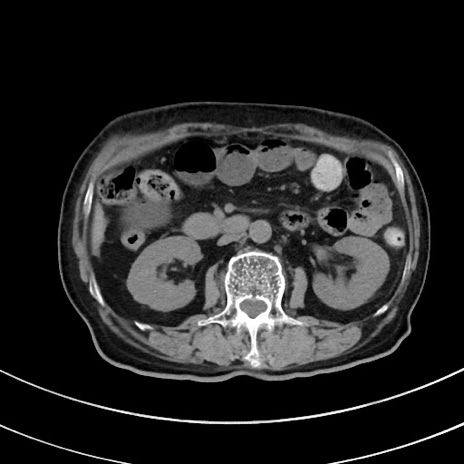

症例33(横断像)

【症例】70歳代 女性

【主訴】心窩部痛

【現病歴】延髄病変の精査・加療にて神経内科入院中。本日より心窩部痛あり。

【身体所見】右下腹部を中心に圧痛と反跳痛あり。

【データ】WBC 10900、CRP 0.02